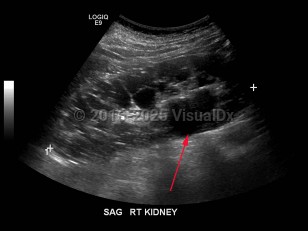

Hydronephrosis

Renal calculus

Polycystic kidney diseasePolycystic kidney disease